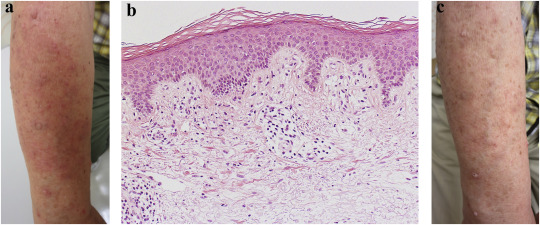

A 65-year-old man was referred to us for consultation regarding a bilateral eruption on his arms. He had a history of chronic renal failure spanning more than 40 years. He had undergone a renal transplantation at the age of 24 years, and received treatment with azathioprine (100 mg daily), prednisolone (5 mg daily), and nifedipine. He had developed a hepatitis B virus (HBV) infection and had been taking 0.5 mg entecavir daily. Six months after taking entecavir, he developed bilateral erythematous plaques on his arms (Fig. 1a). Multiple papillomatous plaques on the arms were verruca vulgaris often seen in the patients after organ transplantation. Laboratory examination revealed increased white blood cell count, 8600/μL (normal range, 3400–7300/μL) without eosinophilia; elevated cholinesterase level, 531 U/L (normal range, 206–476 U/L); and decreased estimated glomerular filtration rate, 45.86 mL/min/1.73 m2 (normal range, >90 mL/min/1.73 m2). Serological test results for the HBV surface antigen and its antibodies were both positive. Histological examination of a punch biopsy specimen from the left forearm revealed superficial perivascular lymphocytic infiltrates with mild vacuolar alteration, which was consistent with a drug eruption (Fig. 1b). Initially, we suspected drug-induced photosensitivity due to nifedipine. However, lesions did not improve even after discontinuation of nifedipine. Minimal erythema doses for UVA and UVB were within normal limits. A drug lymphocyte stimulation test (DLST) results with nifedipine was negative. Based on these results, we suspected that the drug eruption was due to entecavir. DLST with entecavir was performed and the result was positive with a stimulation index of 4.0. Based on the clinical course and the result of DLST, we diagnosed drug eruption caused by entecavir. As the eruption was not severe and entecavir seemed to be effective against HBV, entecavir was not discontinued but reduced to 0.5 mg every second day, and topical corticosteroid treatment was initiated. The eruption gradually improved but did not completely disappear (Fig. 1c).

(a) Clinical findings. Pruritic erythematous plaques on the right arm. (b) ...

(a) Clinical findings. Pruritic erythematous plaques on the right arm. (b) Histopathological findings of erythematous plaque, which show superficial perivascular lymphocytic infiltration with mild vacuolar alteration (hematoxylin and eosin staining, original magnification ×200). (c) Clinical findings 1 month after reduction of entecavir.